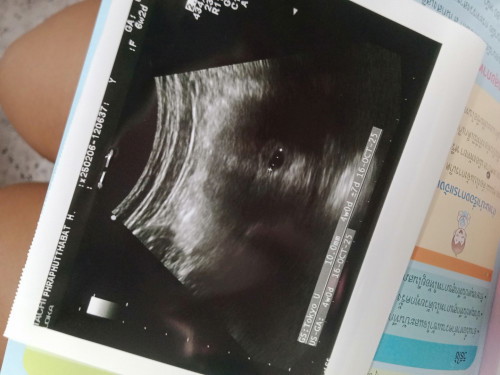

นับตามประจำเดือน6+2 ซาวด์ได้แค่4+0 หมอนัดอีก4สัปดาห์มาซาวด์ใหม่คะ😅

เจอน้องและหัวใจกระพริบๆแล้วค่ะ